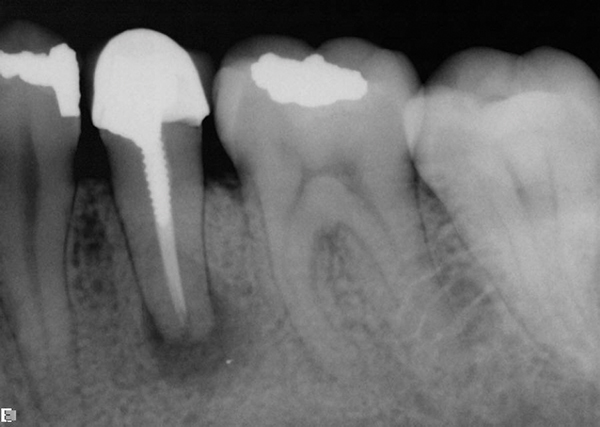

The role of the post is firstly to retain a core restoration and crown and secondly to redistribute stresses down onto the root thereby reducing the risk of coronal fracture. A post and core crown is a type of dental restoration required where there is an inadequate amount of sound tooth tissue remaining to retain a conventional crownA post is cemented into a prepared root canal which retains a core restoration which retains the final crown. Bruising of the gums or skin.

Post and core are custom fabricated as a single unit The post is the part that extends into the root. A post and core crown is a type of dental restoration required where there is an inadequate amount of sound tooth tissue remaining to retain a conventional crown. This can present challenges for both the dental practitioner and the patient in deciding which treatment option suits the patient best taking into account the advantages disadvantages time and cost required to achieve desired results.

A post is cemented into a prepared root canal which retains a core restoration which retains the final crown. The post does not play any role. The post it self is a metallic or reinforced fiber structure that is placed within the root of a tooth that has had a root canal endodontic procedure.